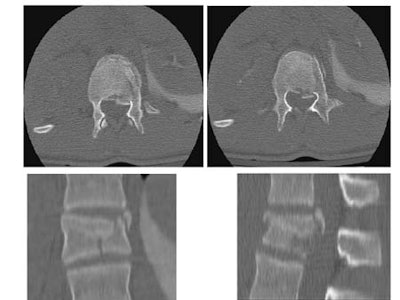

To answer the second question -- Are thoracolumbar spine films necessary after spiral or MDCT of the chest, abdomen or pelvis? -- Novelline turned to a just-published study by colleagues J. T. Rhea et al at MGH (Emergency Radiology, August 2001, Vol.8:2, pp. 99-104).

The study sought to compare the accuracy of spine plain films with chest and abdominal trauma CT in detection of spine fractures in 329 multiple trauma patients.

Thirty-eight patients with 13 thoracic spine fractures underwent both chest CT and plain films. All 13 (100%) of the fractures were reported on chest CT, while only 8 (62%) were seen on thoracic spine films.

Eighty-seven patients with 18 lumbar spine fractures were examined with both abdominal CT and lumbar spine films. Seventeen of 18 were reported on abdominal CT (18th was visible), while only 12 (67%) of the fractures were reported on the lumbar spine films.

![]() |